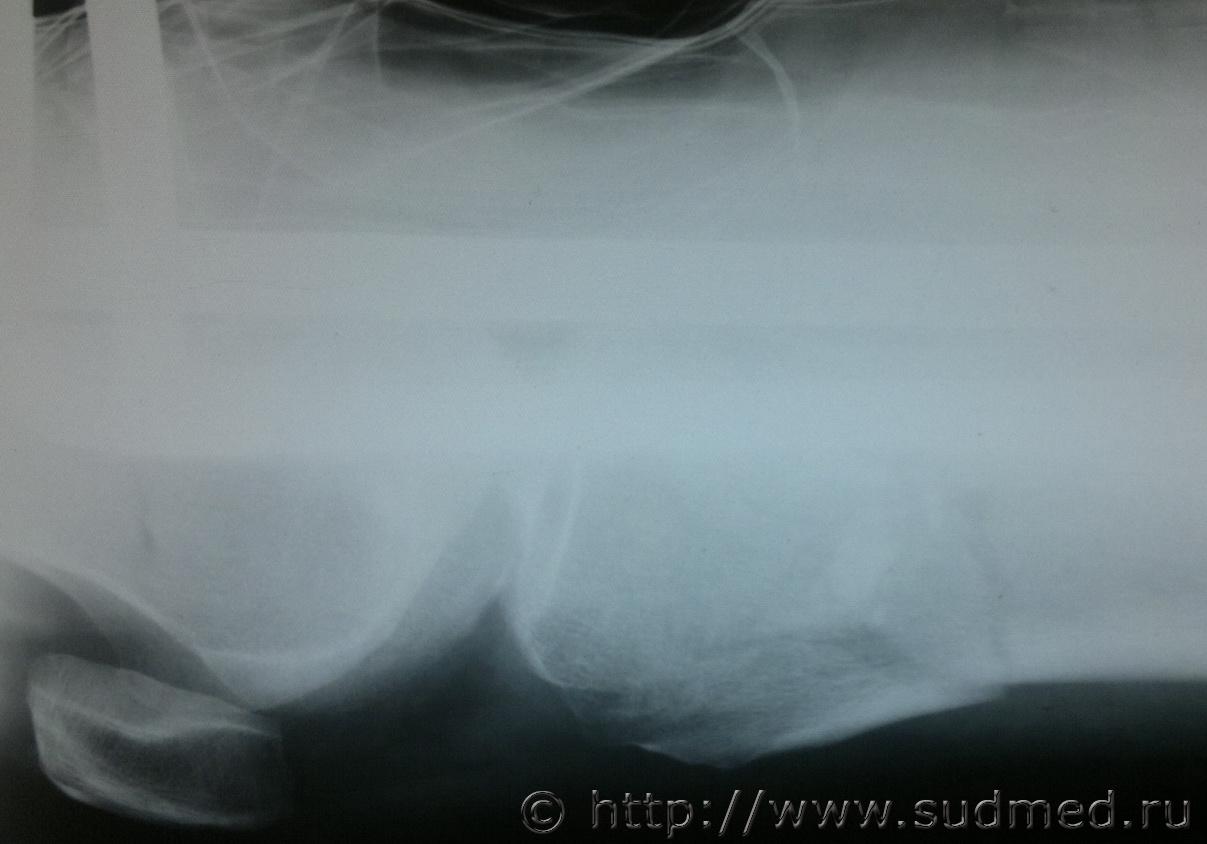

Женщину, 70 лет сбил автомобиль, после чего она была доставлена в ОКБ где были сделаны рентгеновские снимки, которые прилагаю, достаточно ли будет снимков для определения степени вреда здоровью, так как точный диагноз из истории болезни не удалось узнать.Судебная медицина - Прикрепленное изображение Судебная медицина - Прикрепленное изображениеСудебная медицина - Прикрепленное изображениеСудебная медицина - Прикрепленное изображениеСудебная медицина - Прикрепленное изображение

достаточно. Единственное, что по снимку непонятно - открытый или закрытый перелом? В украине это имеет существенное значение для определения степени тяжести, если Вы из России - коллеги точнее скажут, но судя по локализации здесб вроде будут тяжкие телесные

тяжкий вред.

Большое спасибо за быстрый ответ, закрытый перелом обеих ног.